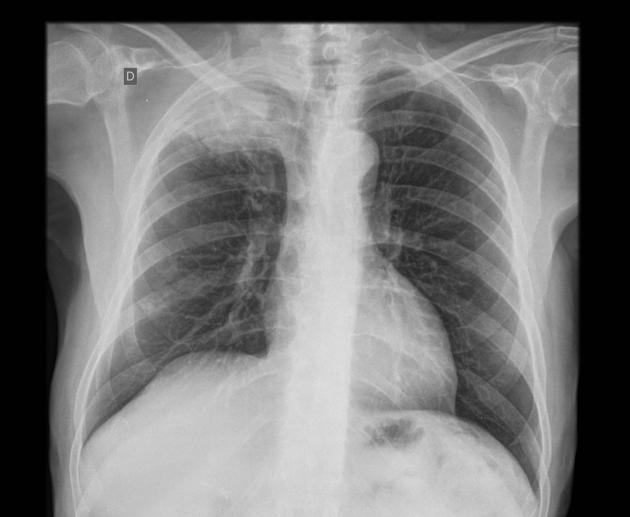

CLINICAL HISTORY:

40Yo Male

SOB for 3/12, pyrexia and cough

FINDINGS:

Bilateral asymmetrical areas of consolidation throughout both lungs, predominantly in the upper and middle zones.

No pleural abnormality is demonstrated.

Heart size is normal. The left hilum is obscured by consolidation, but the right hilum and mediastinal contours are normal.

IMPRESSION:

Appearances are suggestive of an atypical infection or inflammatory process.

BACKGROUND:

This case demonstrates eosinophilic pneumonia. Eosinophilic pneumonias represent eosinophil rich fluid filling alveolar spaces. The cause may be idiopathic, secondary to drug exposure or fungal/parasitic infection, or as part of a vasculitis (Eosinophilic granulomatosis with polyangiitis). Eosinophilic pneumonia can be further divided:

DIFFERENTIAL DIAGNOSIS:

FOLLOW-UP:

Complex pneumonias may need to assessed with HRCT

Blood tests: